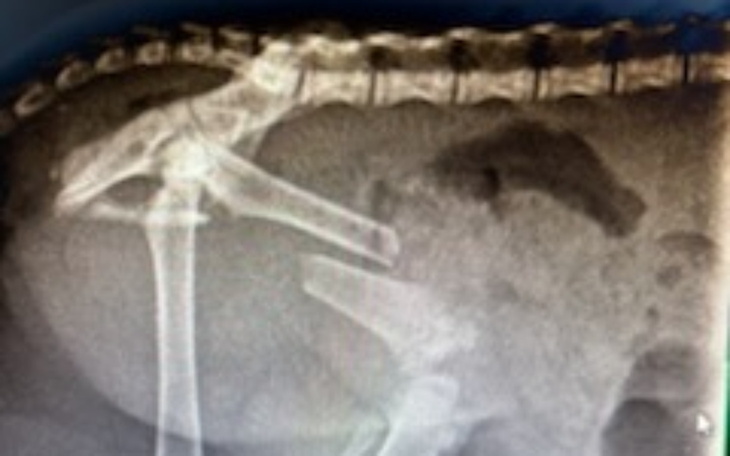

Ktoś podrzucił pani malutkiego 7 tygodniowego , oswojonego kotka na posesję . Kotek leżał w jednym miejscu , nie ruszał się i co się okazało.....maluch ma złamaną tylną łapkę . Potrzebna jest pilna operacja ....poproszono nas o pomoc . Nie mogliśmy odmówić . Kotkiem na okres wyzdrowienia zajmie się pani i poszuka mu domu .